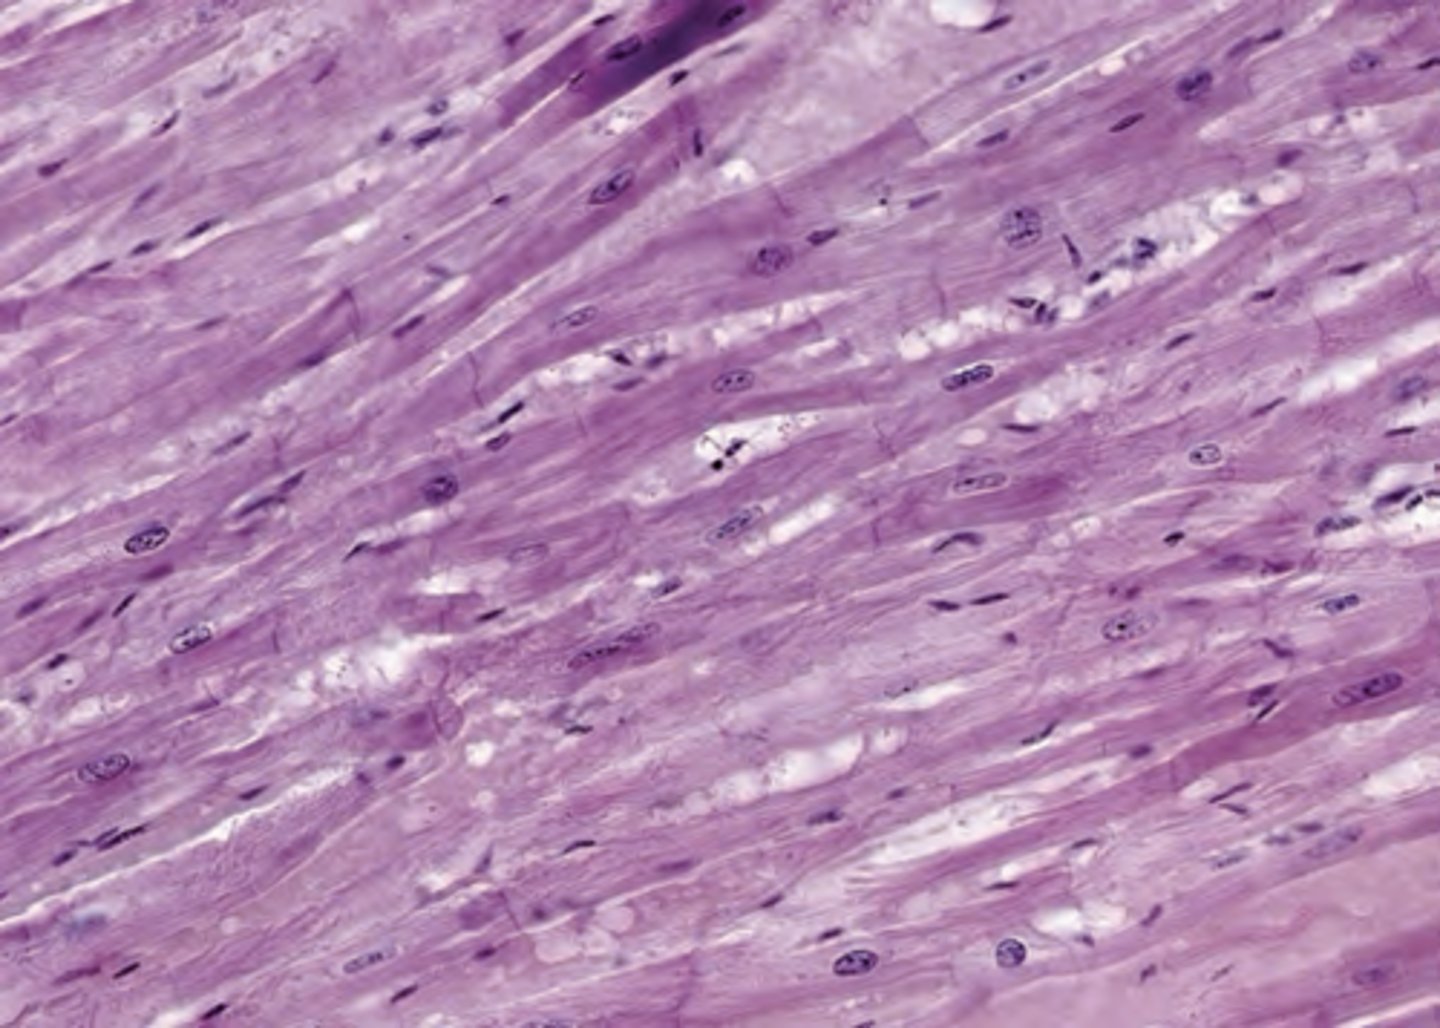

A 40-year-old woman with a suspected disorder undergoes a muscle biopsy. The microscopic image, shown above demonstrates the tissue after processing and staining. Which of the following best describes this tissue biopsy?

A. Non-striated muscle with peripheral nuclei stained with hematoxylin and eosin

B. Non-striated muscle with a single, central nucleus stained with hematoxylin and eosin

C. Non-striated muscle with peripheral nuclei stained with Periodic acid-Schiff

D. Striated muscle with a single, central nucleus stained with hematoxylin and eosin

E. Striated muscle with peripheral nuclei stained with hematoxylin and eosin

The answer is E. This image shows skeletal muscle, which is a striated muscle with peripheral nuclei. The image is stained with hematocylin and eosin.